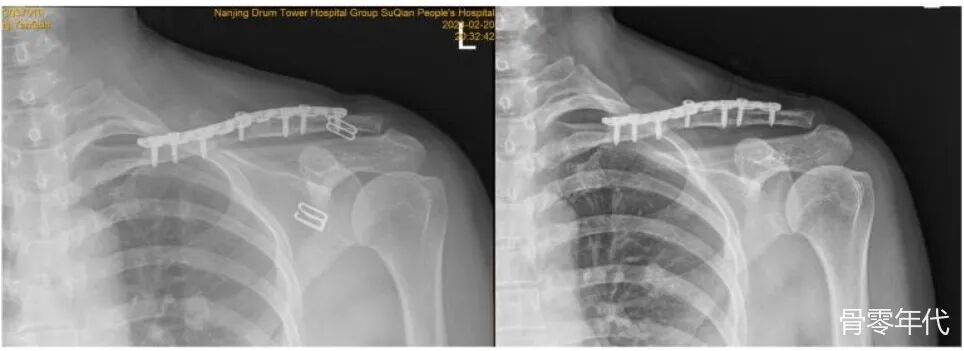

术前X线检查提示左锁骨中段骨折,移位明显。术后X线:显示内固定到位,骨折对位良好。术后4个月X线片:骨折线仍清晰可见,提示骨折愈合延迟。术后11个月X光片:骨折线仍然清晰可见,这可能表明骨折尚未完全愈合或愈合过程停滞。术后17个月X光片:未见明显骨折线,通常表示骨折已愈合。拆除内固定后:骨折端移位,这意味着发生了骨折。切开复位和骨移植内固定后的X射线。